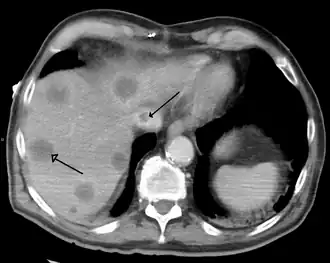

- Budd–Chiari syndrome is the clinical picture caused by occlusion of the hepatic vein.[19]